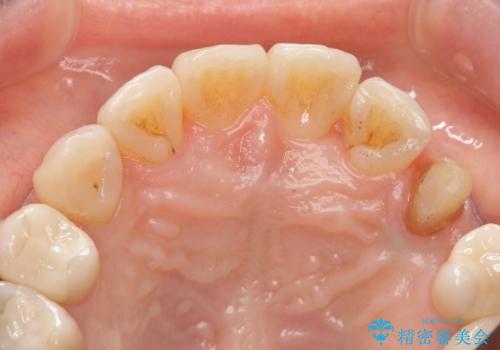

- 左上犬歯の一部が歯ぐきの中まで虫歯になっており、部分矯正をして歯を引っ張り出しました。(エクストリュージョン)

左:虫歯を除去したところ。遠心が歯ぐきより深い状態です。中:そのままかぶせようとすると、遠心が歯ぐきが腫れやすい状態です。右:エクストリュージョンをしたことで、遠心の歯ぐきの腫れが収まっていることがわかります。

エクストリュージョンをしたことで、いくら歯磨きを頑張ってもどうしても腫れてしまう歯肉に対して、歯周囲組織の位置関係を変えることで根本的に解決しました。